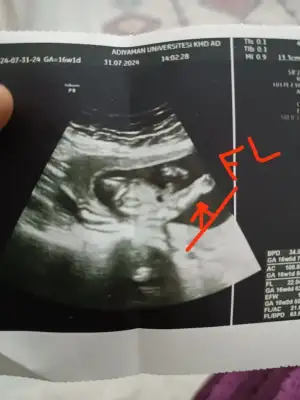

Kızlar bugun kontrole gittim devlete bir umut kız der diye oda erkek dedi 😂 birde bu usg fotosunu verdi ne neresidir bir türlü çıkaramadım bir sizde bakın yaa ölçtüğü kısıma fl demiş benim bildiğim fl de boydan boya uyluk kemiğinin ölçümü

Canım o işaretlediğin yer bacak bence 🥰 maşallah kuzum sağlıkla gelsin ❣️